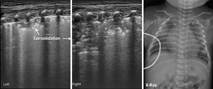

本组MAS患儿的肺脏超声主要表现(表1):(1)肺实变伴支气管充气征:见于所有患儿,重度患儿通常为范围较大、且边界不规则(锯齿状边缘)的实变区(图2,图3,图4);而轻度患儿则以小范围的局限性实变为主要表现(图5);但双侧肺脏实变范围的大小可以不同,而且同一侧肺脏野可以存在大小不同的实变区(图4,图5,图6)。(2)胸膜线异常与A-线消失,见于所有患儿,胸膜线异常表现为病变区胸膜线消失或增粗模糊(图2,图3,图4,图5,图6)。(3)肺不张,是严重肺实变的表现,见于重度患儿,本组12例(17.9%)(图7),严重大面积肺不张时可在实时超声下见到肺搏动和动态支气管充气征。(4)胸腔积液,见于9例(13.4%)患儿(图7)。(5)B-线或AIS,在实变区以外肺野则以AIS或B-线为主要表现。

MAS具有典型的肺脏超声影像学改变。主要特征如下:(1)肺实变伴支气管充气征,见于所有患儿。通常重度患儿实变范围较大、边界不规则呈锯齿状,支气管充气征也较为明显;而轻度MAS则为较小范围的局灶型实变。(2)双侧肺脏或同一侧肺脏不同肺野病变性质与程度的不一致性,双侧肺脏可有范围不同的实变区,同一侧肺脏不同肺野也可以存在大小不同的实变区。(3)肺不张,见于少数重症患儿,更为严重者在实时超声下可见肺搏动或动态支气管充气征。(4)胸膜线异常,表现为病变区胸膜线消失或增粗、模糊。(5)A-线消失,所有患儿在实变区和非实变区均不见A-线。(6)B-线或AIS,非实变区肺组织在超声下常表现为B-线或AIS。(7)胸腔积液,轻度或重度MAS患儿均可有胸腔积液,本组见于13.4%的患儿。但上述超声表现也可见于RDS、肺不张和TTPN等肺病,虽均非MAS的特有改变,但均有各自的特点,超声很容易对它们做出诊断和鉴别诊断[4,5,6,7]。但在肺炎、尤其重度肺炎时,肺脏超声也表现为边界不规则的大面积肺实变[7,15],如无一定经验,仅靠超声表现有时难以将二者准确区别。因此,在借助超声诊断MAS与重症感染性肺炎时,往往需要结合病史。